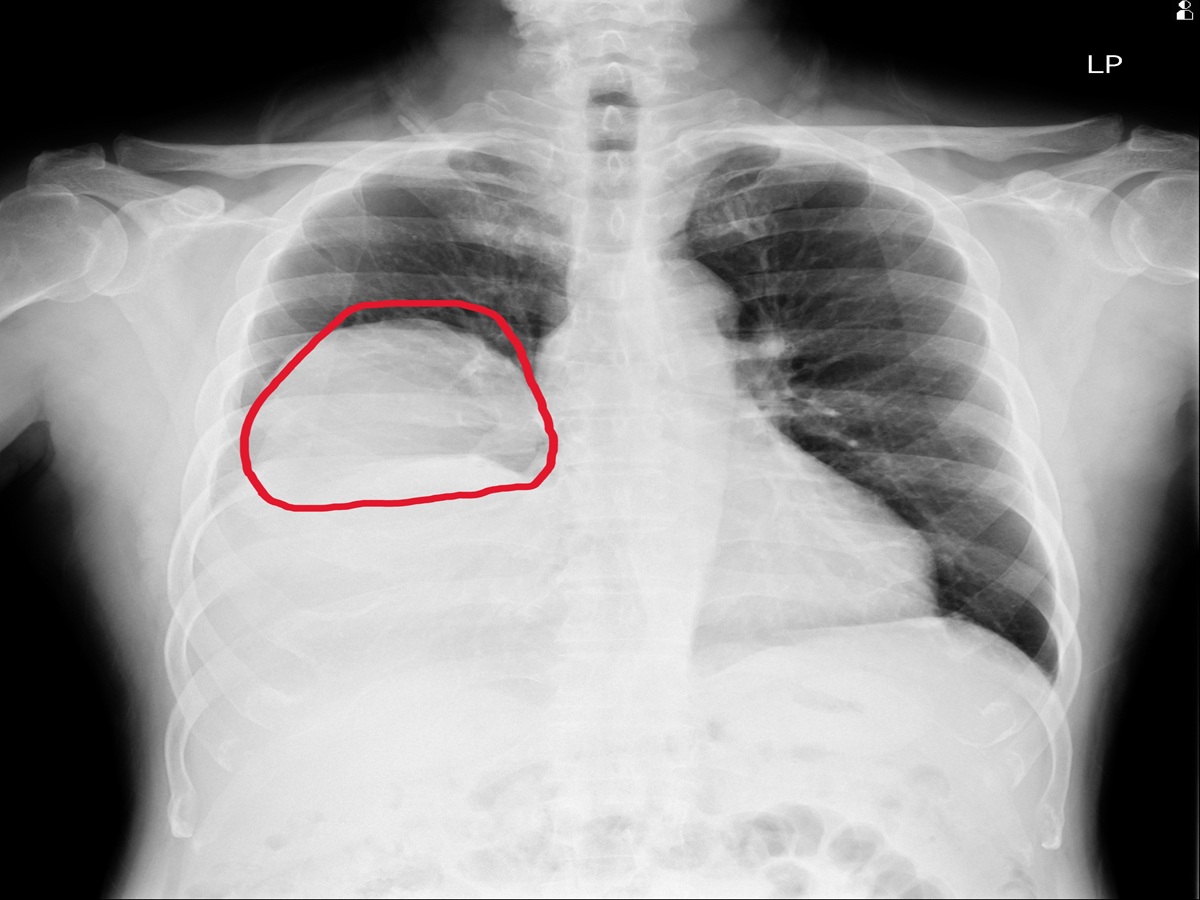

住院期間,患者仍頻繁出現低血糖發作,甚至血糖多次低於30 mg/dL,需持續補充高濃度葡萄糖維持穩定。進一步透過胸部X光與電腦斷層檢查,發現右肺有一顆巨大腫瘤,影像顯示約15×11公分,且壓迫周邊結構,並伴隨肋膜積液與淋巴結腫大情形。

因此會診胸腔內科醫師涂川洲副院長,醫療團隊評估後高度懷疑為「腫瘤相關低血糖」,可能與腫瘤分泌類胰島素生長因子(IGF-2)有關,屬於罕見的「非胰島素瘤性低血糖症(NICTH)」。此類情況多見於大型腫瘤,尤其是間質性或纖維性腫瘤。

術後病理報告確認為罕見的「肺部單發性纖維瘤」,此類腫瘤並不常見,且約有5%的患者會合併低血糖症狀,屬於典型的腫瘤伴隨症候群表現。